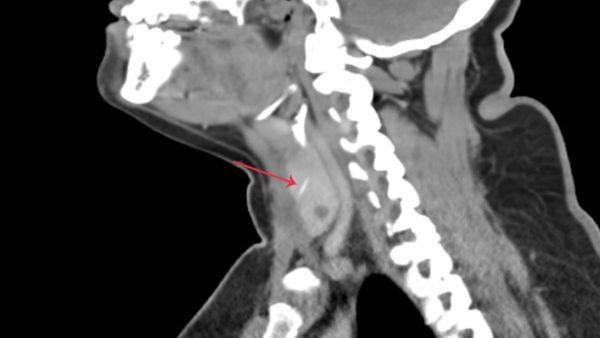

Initial examinations using a laryngopharyngoscope revealed no visible foreign body. However, a subsequent sonogram identified a suspicious linear object, leading to her referral to Aster Hospital Mankhool. A CT scan with contrast confirmed the presence of a 3cm fish bone embedded in the right thyroid lobe, penetrating the strap muscle.